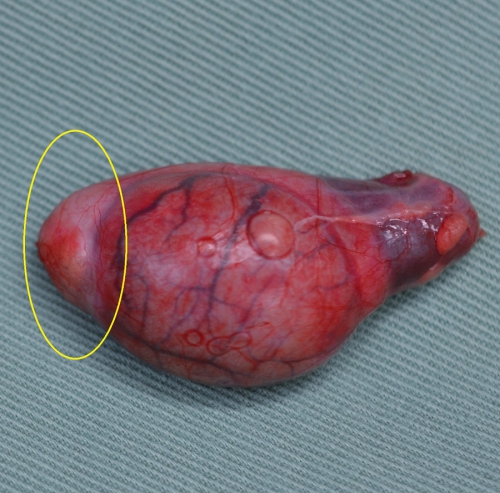

下の写真が精巣・精巣上体炎を起こした犬の精巣上体を黄色丸印で示しています。右が正常、左が精巣上体炎の見られた睾丸です。2週間程度の抗生物質による治療後にも痛みと腫れが残ったため、症状の緩和のために去勢手術を実施したものです。当初の著しい腫れは見られませんが、全体的にかなり赤みを帯びており、精巣上体は明らかに硬い印象がみられました。